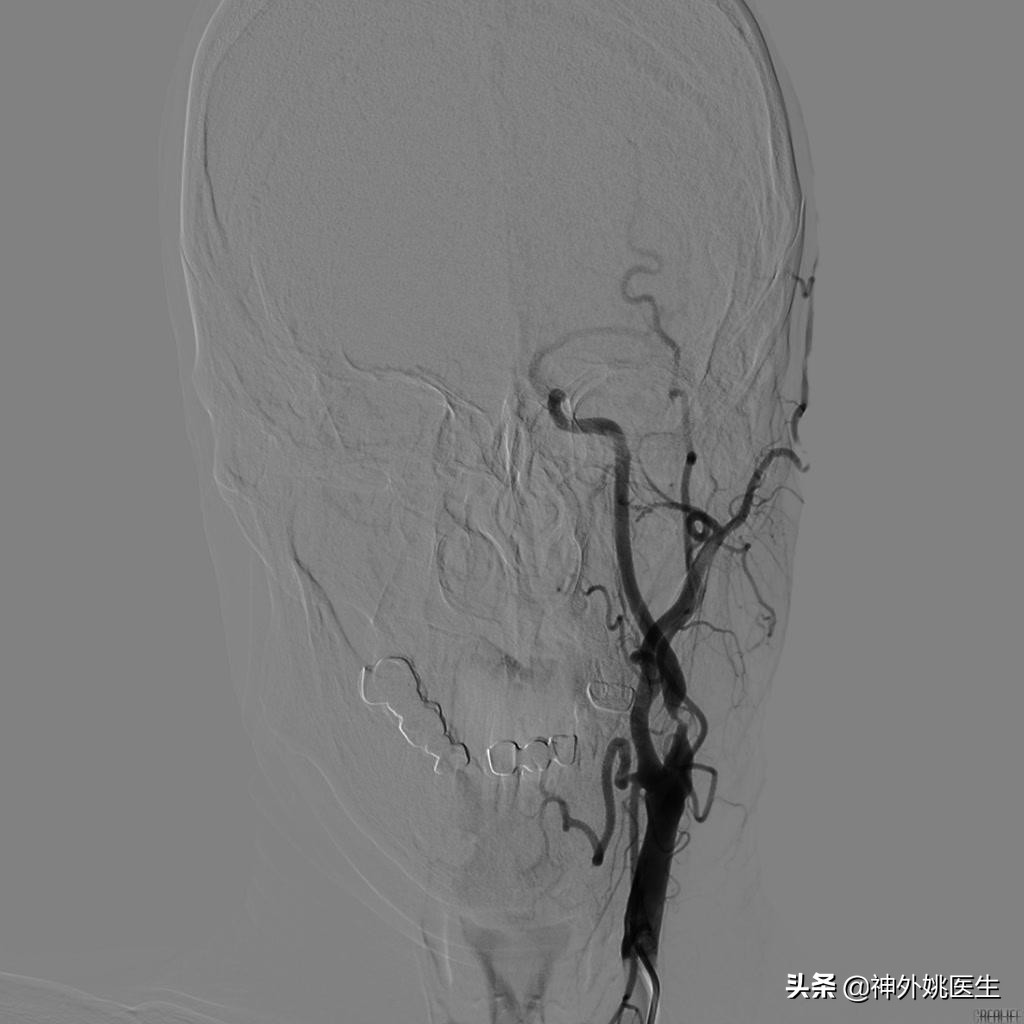

术前DSA检查:(图3-6)

图3 左颈内动脉起始段重度狭窄。

图4 右颈动脉造影示前交通动脉开放,左侧A2以远显影,通过左侧A1至M1以远亦显影。